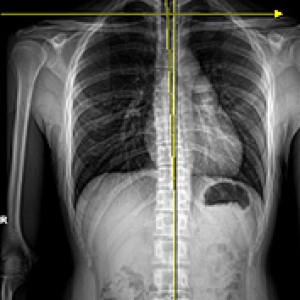

Before & After

해당 사진은 수정없는 실제 치료사진입니다.

환자의 치료결과는 환자의 상태, 치료방법 등에 따라 차이가 발생할 수 있습니다.